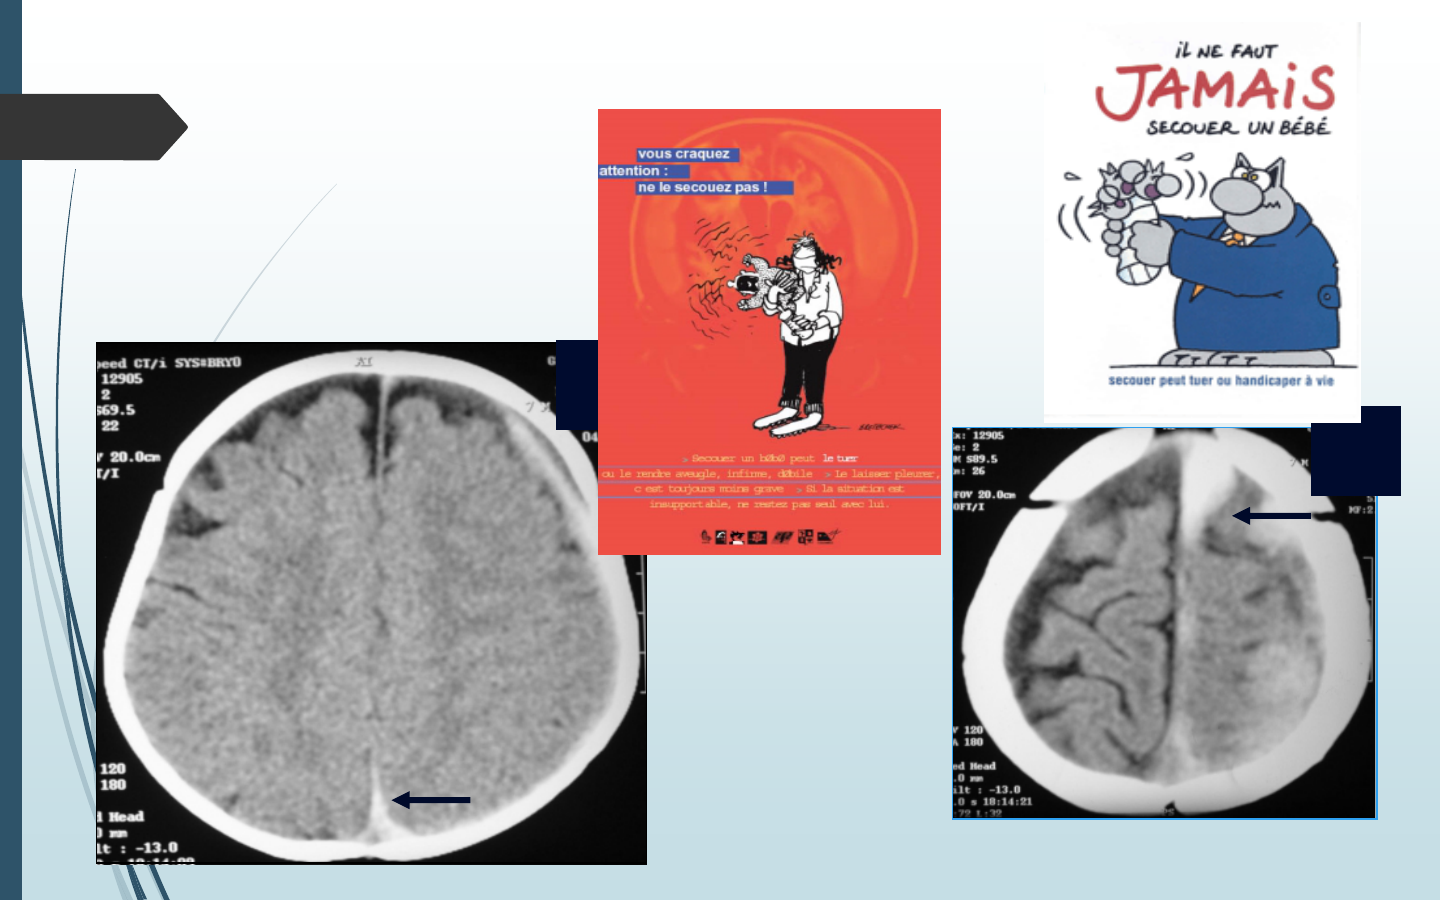

T Traumatisme (crânien-HSD -HTIC, fracture)